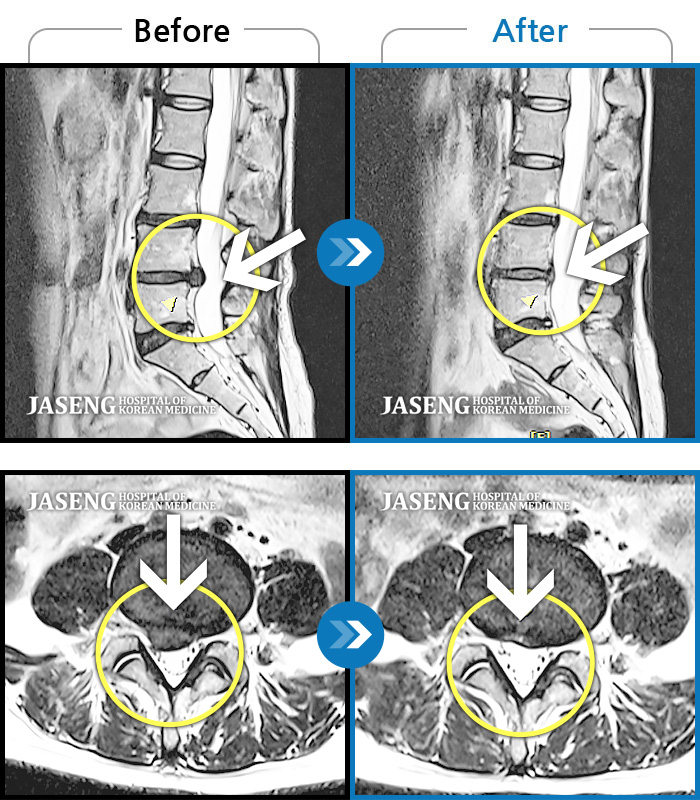

허리디스크

광주 · 김동은 원장

허리부터 골반 및 우측 허벅지에서 발가락까지 묵직한 통증과 저림 발생하여 내원하셨습니다.

촬영시기

2022.07.22 ~ 2025.08.18

2025.08.22